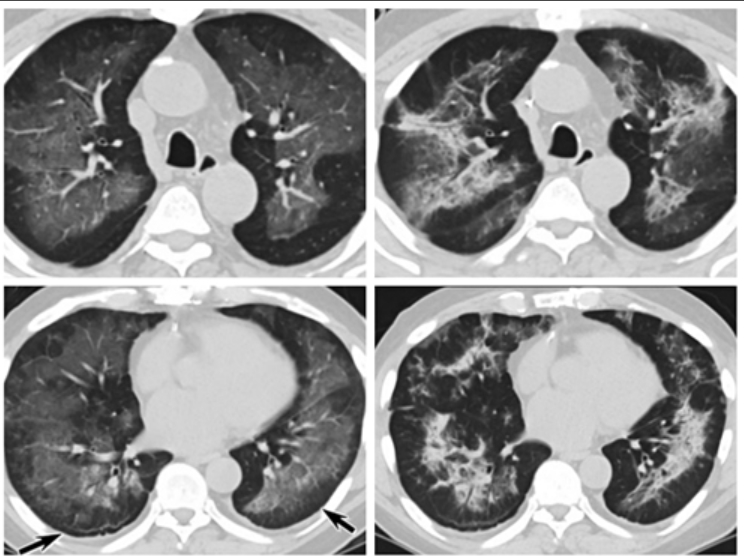

Koronavirus na snímcích plic amerických pacientů z roku 2019?

Když vzniknou nové nakažlivé choroby, je to vždy zdlouhavá pečlivá práce, která vede k vystopování jejich původu. (Foto: Twitter)

Jednou ze záhadných chorob, která se náhle objevila, a lékaři ji nechápali, byla plicní choroba z kouření e-cigaret, která roku 2019 zachvátila 50 amerických států. Jenže podle skupiny čínských výzkumníků a radiologů, kteří prozkoumali 250 CT snímků z publikovaných článků o záhadně se roku 2019 v USA šířící nemoci z e-cigaret (EVALI), řada obrázků vypadá úplně stejně, jako by ti lidé měli COVID-19.

Čínský výzkumný tým, který na tom pracuje, tisku vyzradil, že zkoumal 250 CT skenů od 142 pacientů s EVALI z 60 publikovaných studií. Přitom podle čínských výzkumníků alespoň 16 EVALI pacientů muselo mít ve skutečnosti virovou infekci a u pěti dalších je na to podezření. Přitom ta virová infekce vypadá přesně, jako by šlo o COVID-19.

Všech 16 EVALI pacientů, u kterých v tom byly určitě viry, bylo z USA a 12 onemocnělo v průběhu roku 2019.

Určitě by stálo zato prověřit, zda ty ze snímků vytipované případy EVALI byly opravdu ranými projevy rozbíhající se infekce v USA už roku 2019, a tak by to bylo při normálním vědeckém přístupu standardní.

Roku 2019 ještě nebyly k dispozici virové testy nukleových kyselin odhalující tuto chorobu, a tak je normální, že všichni její nositelé byli diagnostikováni běžnými chorobami s podobnými příznaky a není se co divit, že lidi se zápalem plic kvůli COVID-19 diagnostikovali jako pacienty s EVALI. Teprve, když divná epidemie zvláštních „chřipek“ a pneumonií vypukla v ohromném měřítku ve Wuhanu za dveřmi genetické laboratoře, koukli se na to výzkumníci přes geny, aby zjistili, co je to za novou chřipku, a s ohromením objevili nový koronavirus.

Ty CT skeny jsou samozřejmě jen prima facia důkazem, ale ani když někoho po střelbě chytí s kouřící zbraní v ruce, není to ještě konečný důkaz, že střílel on. A tak by bylo záhodno, aby na tato zjištění čínských výzkumníků navázali jejich kolegové v USA a začali dělat testy krve těch pacientů s EVALI na protilátky ke zjištění, kolik jich mělo ve skutečnosti COVID-19. A pokud takové prověřování probíhat nezačne nebo se jeho výsledky nebudou normálně zveřejňovat, musí to zákonitě budit silné podezření.